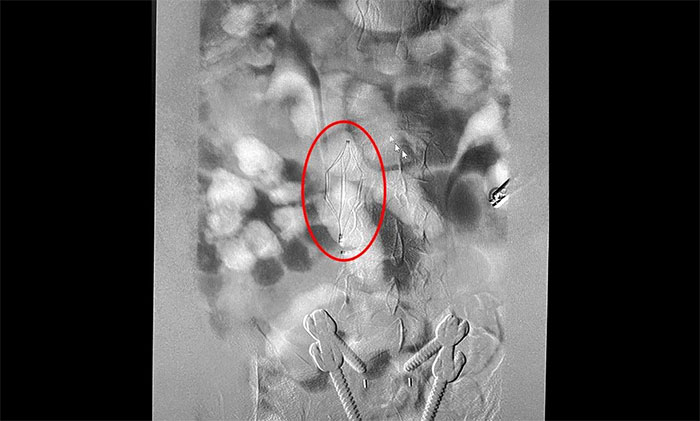

12月15日,席刚明教授在王贵平博士及介入团队协助下顺利行将一个形似伞状的人工滤器经患者右侧股静脉穿刺迅速置入肾静脉下方,“网”住了通往心血管和肺部的致命栓子,阻挡血液栓子进入肺动脉,及时挽救了患者生命。之后对病变血管进行了血栓抽吸术,及接触性溶栓,抽出了大量血栓,复查下肢造影示血栓基本消失,下肢静脉血管再通,整个手术顺利完成。术后,患者下肢肿胀好转。

▲ 下肢深静脉血栓形式